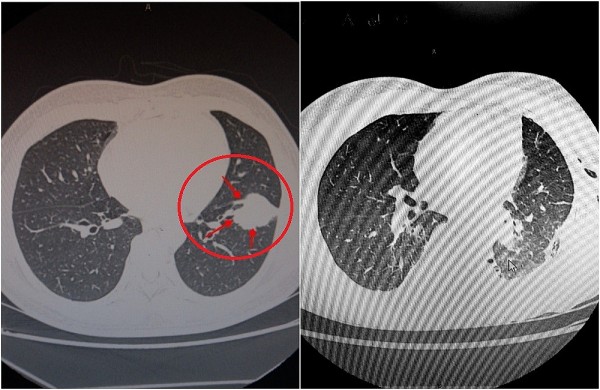

Hút thuốc lào gần 30 năm: Người đàn ông phát hiện mắc ung thư phổi

SKV – Qua khai thác, bệnh nhân cho biết đã hút thuốc lào gần 30 năm, không có bệnh lý kèm theo. Kết quả chụp cắt lớp vi tính cho thấy, nhu mô thùy dưới phổi trái của người bệnh có khối u đường kính hơn 4cm.